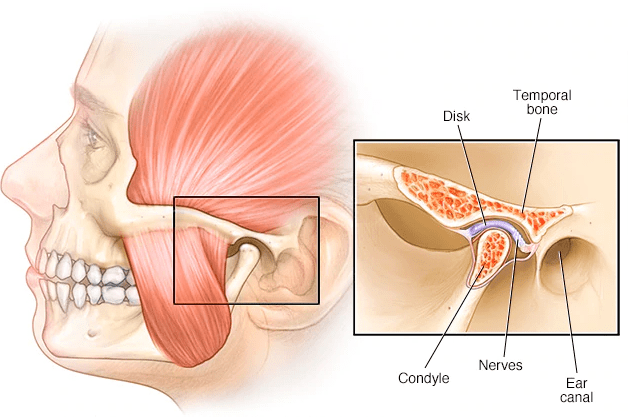

A gnatológia a fogászat talán leggyorsabban fejlődő és egyik legújabb területe, amely az állkapocsízület (TMI) helyzetével, annak mozgásaival, problémáival (TMD) foglalkozik. Amíg nincs vele problémánk, nem is tudjuk, nem foglalkozunk vele, hogy van ilyen ízületünk, pedig a rágás és a beszéd bonyolult állkapocsmozgásait ez biztosítja, és egyben kapcsolatot teremt az állkapocs és a koponya között.

Amikor az állkapocsízület valamilyen rendellenes mozgás, feszülés, nyomás miatt sérül, deformálódik, kopik, az megnyilvánulhat fültájéki tompa, esetenként heves fájdalomban, szájnyitási rágási nehézségekben, az állkapocs mozgását kísérő kattogásban, furcsa, recsegő-ropogó hangokban, fülfájásban, illetve migrént, fülzúgást is okozhat, emellett alvászavarok kiváltó oka lehet. Mivel a tünetek hosszú távon alakulnak ki, ezért gyakran a javulás, gyógyulás is sok időt vesz igénybe. Több hónapig is eltarthat, türelmet igényel mind a páciens, mind az orvos részéről, de általában látványos eredménnyel zárul.